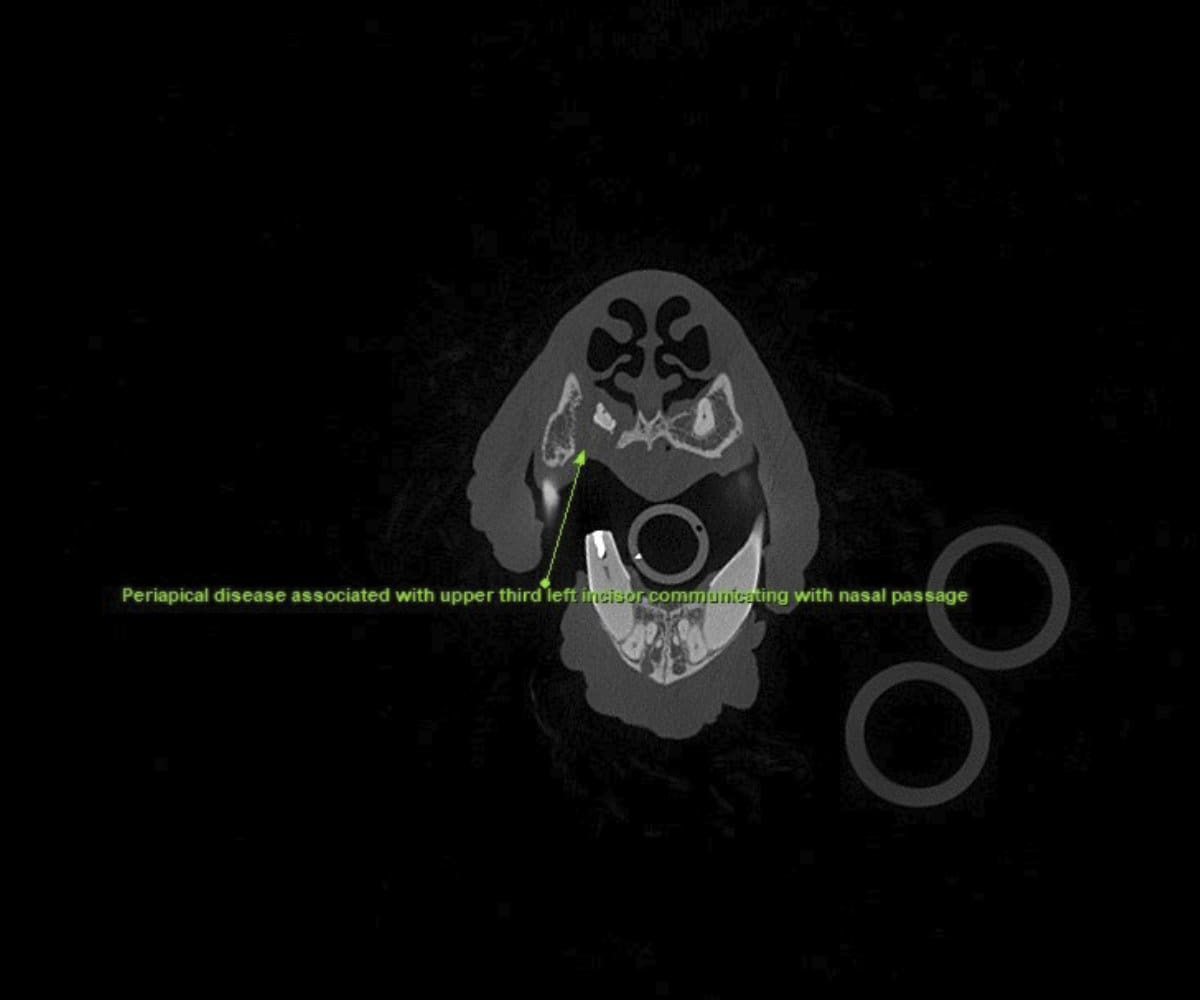

In addressing these limitations, CBCT emerges as a pivotal advancement. Conducting a CBCT scan on our patients is characterized by minimal time and effort, effectively reducing anesthesia duration. Moreover, this technology facilitates the generation of a comprehensive 3D reconstruction of the teeth and skull, surpassing the constraints of traditional radiographs. This innovative approach empowers our veterinary professionals to identify oral pathologies that may have been missed on traditional radiographs.

Cone beam CT technology provides veterinarians with 3-dimensional images in far greater detail than dental radiographs. CBCT scans significantly decrease the amount of time a patient spends under anesthesia compared to the time it takes to complete dental radiographs.

Our CBCT VetCAT unit is easily rolled up to our treatment table and takes only 40 seconds to complete a scan. It has proven to be invaluable in the diagnosis and treatment planning for pets with periodontal, endodontic and cancerous disease conditions. It is also indispensable in the evaluating our trauma cases with jaw fractures.